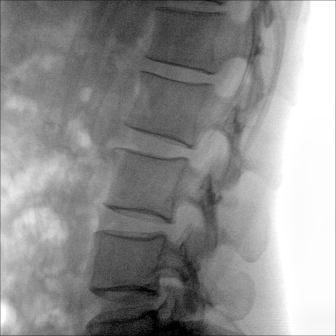

大尺寸動(dòng)態(tài)平板探測(cè)器,高DQE、低噪聲、圖像清晰。采用多分辨率圖像增強(qiáng)處理技術(shù),不同部位不同圖像處理算法,滿足客戶多樣化的需求。

采用智能變頻脈沖透視技術(shù),優(yōu)化圖像質(zhì)量的同時(shí)降低輻射劑量,呵護(hù)醫(yī)患健康

多角度自由旋轉(zhuǎn),滿足患者復(fù)雜擺位需求。